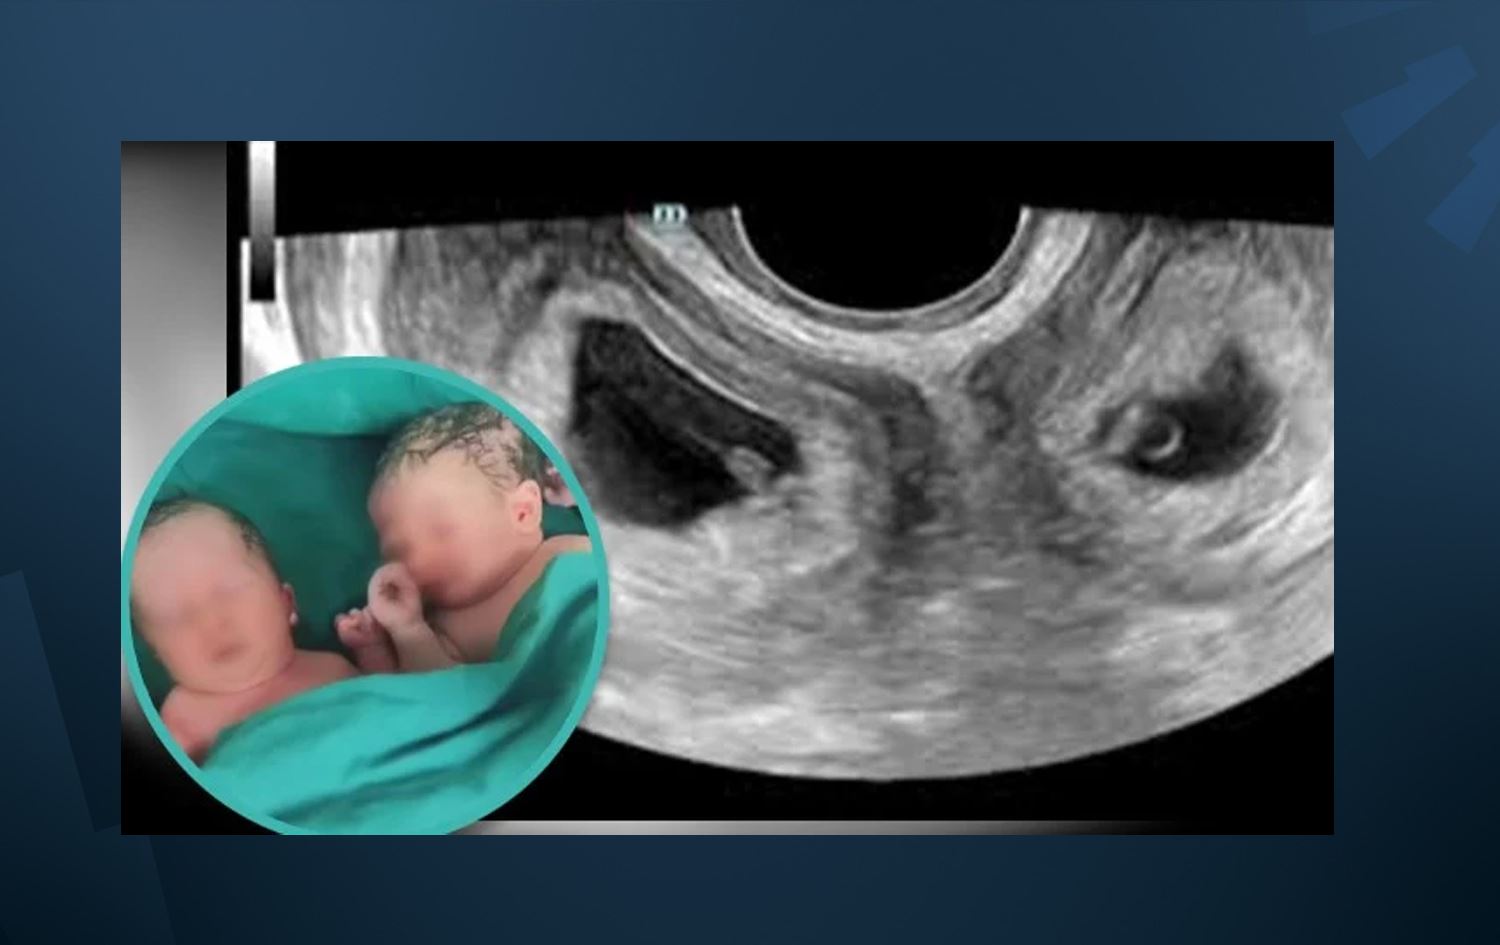

خانمێک لە چین دووانەیەک {کوڕێک و کچێک}ـی بە دوو منداڵدانی جیاواز دەبێت و ''هەردوو منداڵەکە تەندروستن''.

خانمەکە ناوی لییە و د. چای یینگ، پسپۆڕی نەخۆشییەکانی خانمان و منداڵبوون لەو نەخۆشخانەیەی هەرێمی شانکسی کە خانمەکە دووانەکانی لەدایکبوون، دەڵێت: کوڕێک و کچێکی بووە کە هەریەکەیان لە منداڵدانێکی جیاوازی خانمەکە گەشەیان کردووە.

ئەو پسپۆڕە دەڵێت، دووگیانیی خانمەکە هەشت مانگ و نیوی تێپەڕ کرد و توانراوە بە نەشتەرگەری منداڵەکان بە سەلامەتی دەربهێندرێن.

بەپێی ناوەندی کلڤیلاندی پزیشکی، بوونی دوو منداڵدان دۆخێکە پێی دەگوترێت didelphys کە 0.3٪ـی خانمان دوو منداڵدانیان هەیە و ئەگەری تووشبوونیان بە 'لەبارچوون، منداڵبوونی پێشوەختە، خوێنبەربوون و چەندان کاریگەریی لاوەکیی دیکەش' هەیە.

هەر بەپێی ناوەندەکەن، هەر منداڵدانێک جۆگەی هێلکە و هێلکەدانی تایبەت بە خۆی هەیە، تەنانەت هەندێک سەرچاوەش دەڵێن، حاڵەتەکە ئەوەندە دەگمەنە کە لەکۆی ملیۆنێک منداڵبوون، رەنگە یەک منداڵبوونی لەو شێوەیە رووبدات.